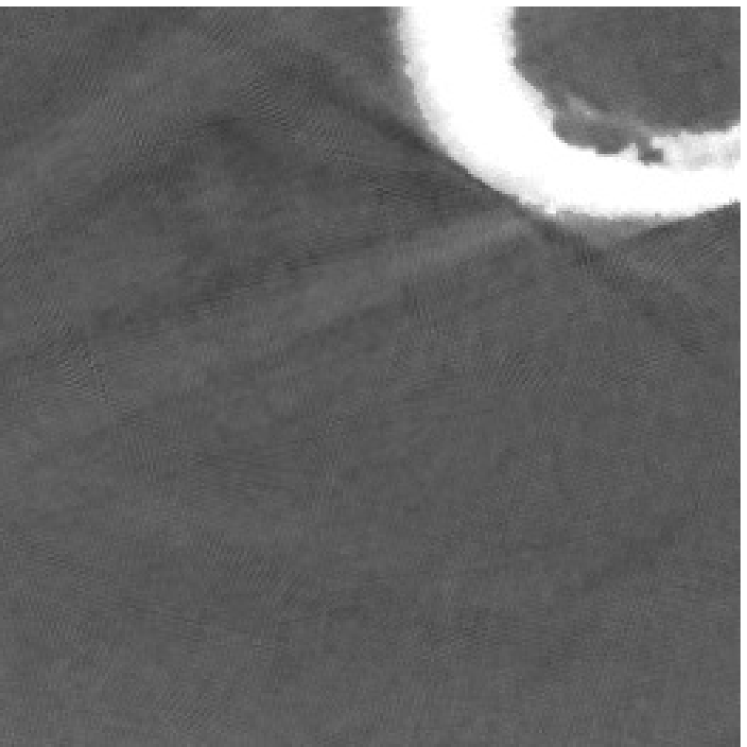

4.2 Numerical experiments: real data

We perform a CT scan of a chicken leg placed in a disposable cup (Figure 10(a)). We first scan the chicken leg without metals (Figure 10(b)) to create a reference image using FBP algorithm. Then, we place two steel thread nails on each side of the chicken leg and scan the subject again using the same scanning protocol (Figure 10(c)). The projection data is acquired from a MicroCT scanner equipped at the Division of Nuclear Technology and Applications, Institute of High Energy Physics, Chinese Academy of Sciences. The X-ray source is with 90 kV and 70 mA energy and the flat plane detector contains pixels. The scanning trajectory is a full circle with equally spaced views at per view. The physical size of each detector unit is . The distance from the X-ray source to the detector is . In order to conduct a 2D experiment, we choose the 512th row of the detector array.

Figure 11 shows the images reconstructed using FBP, the analysis model (2.12), the inpainting model (2.13) and the segmented image from the image obtained by (2.14). The reference image without metal implants are shown in Figure 11(a). All the images in this subsection are displayed within the grayscale interval . The segmented image shown in Figure 11(e) is used to estimate the weights needed in NMAR and the re-weighted JSR model.

Figure 12 shows a comparison between the reconstructed image from NMAR and the unweighted JSR model. Figure 13 shows a comparison between the reconstructed images from TV-FADM and the proposed re-weighted JSR model. Zoom-in views are provided in both Figure 12 and Figure 13 for a better visual assessment. As one can see that the reconstructed images from the unweighted JSR model and TV-FADM are less noisy than NMAR as indicated by the blue ellipse curve, whereas NMAR does a better job in preserving image features and suppressing metal artifacts. However, there are also new artifacts around the metal on the right as shown in Figure 12(d). The proposed re-weighted JSR model has best overall performance in terms of feature preservation, noise and metal artifact reduction.